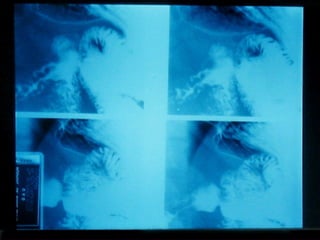

SEGD La impresión radiológica básicamente se divide en tres limitados y un difuso Ulceración Estrechez Masa Compromiso difuso por ulceración y/o engrosamiento  parietal

SEGD La impresiónradiológica básicamente se divide en tres limitados y un difuso Ulceración Estrechez Masa Compromiso difuso por ulceración y/o engrosamiento parietal